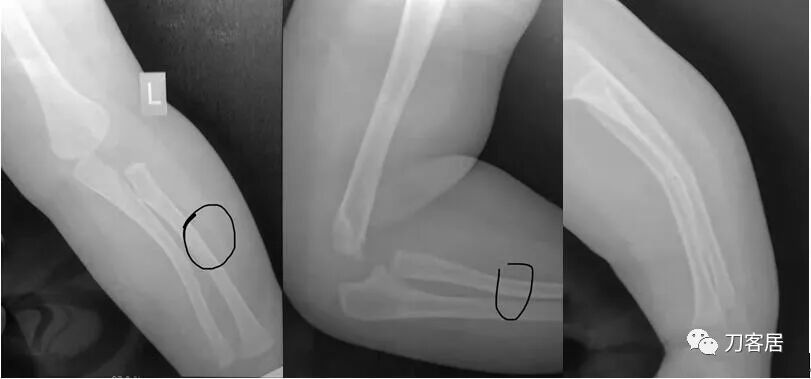

下面是这个6岁孩子,尺桡骨远端双骨折的术前及术后片子和外观照片。

1.  这是一个很简单的6岁儿童无移位的尺桡骨远端骨折。没有皮肤损伤,没有移位,没有骨折碎块儿。

2.  这个骨折处理起来也很简单,单纯的打石膏托或者中医的小夹板,或者正规的包括腕关节和肘关节的管型石膏外固定4周即可治愈该骨折。实在不行,如果这个孩子比较听话,不太调皮的话,用一本书,一个三角巾悬吊固定4周,都可以治愈该骨折。但是给这个患者用外固定架做了手术,而且桡骨远端的几颗克氏针距离骨折线太近,其中一枚克氏针进入到骨折间隙内。从这个术中图片来看,术者的外固定手术技术也有待于进一步的提高。毕竟术者应该还很年轻。从X线片来看,前臂及手的尺侧有不透光影,应该还使用了外固定石膏绷带托,而且我猜测应该是高分子的石膏绷带托,这个是纯属猜测,不一定是对的,不过如何解释前臂尺侧的不透光影呢?如果真是用了石膏绷带外固定的话,那为啥要做手术呢?外固定架术后就不该再用石膏绷带托辅助了。

3.  对于肢体骨折,特别是前臂长骨骨折,双骨折虽然不稳,但更容易手法复位,往往单骨折手法复位比较困难。该病例患儿6岁,尺桡骨双骨折,没有移位,所以根本就不存在需要复位的,直接打石膏外固定即可。孩子年龄越小,塑形能力越强,愈合速度越快,即使是有轻度的畸形骨愈合,在未来的塑形过程中,自然而然的恢复正常的力线和功能。对于该病例,即使是不干预,再过1-2周,只要骨折断端不移位,也能正常愈合而不留任何畸形。